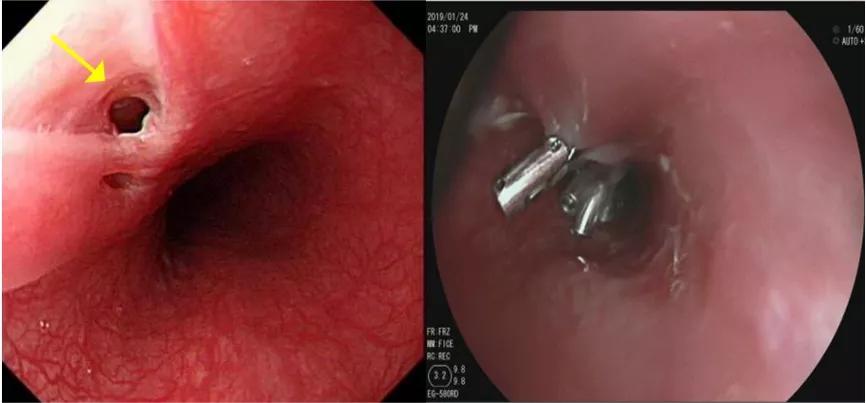

入院第五天,无痛胃镜检查:“食管内距门齿30cm处见一直径约0.5cm瘘口,金属夹夹闭,放置小肠营养管”。

果然!

检查结束回到病房,医生跟大梅两口子宣布了确诊的喜讯,大梅老公抱着刚从麻醉中苏醒还有些没力气的大梅,二人相拥而泣。

确诊之后,大梅的吃饭问题需要通过营养管解决,食物通过营养管直接进入小肠,给食管上的伤口一段时间愈合恢复,然后才能恢复正常饮食。